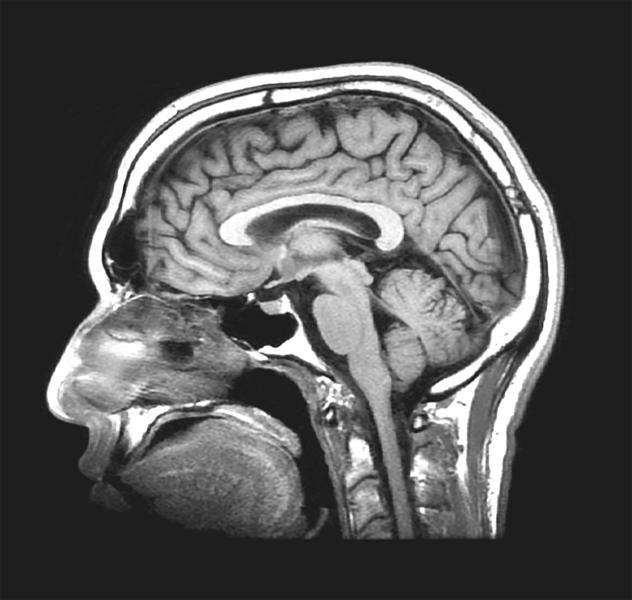

A greyscale image of a cross-section scan of a head, showing the brain

A member of John Gabrieli’s lab, MIT PhD student Omar Rutledge uses MRI images, such as this one of a veteran with PTSD, to research the connection between trauma and the mind.